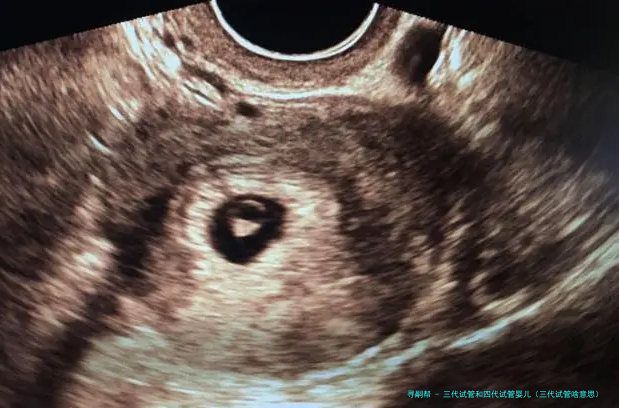

试管婴儿的医学术语称:胚胎转移技术-胚胎移植,其过程是女的一方先使用药物促排卵,再从卵巢内拿出卵子,男方拿出精子,在实验室将精子、卵子结合培育成胚胎,然后又将胚胎转至子宫腔内,令其着床、妊娠。

试管婴儿道理 “试管婴儿”其实不是真正在试管里长大的婴儿,而是从卵巢内拿出若干个卵子,在实践室里使之们与男方的精子结合,形成胚胎,然后挪动转移胚胎到子宫内,让它位于妈妈的子宫内着床、妊娠。

试管婴儿的道理实际上其实不繁复。在正常情况下,受孕过程是由精子进入女的一方身体内,到达输卵管,在输卵管的壶腹部与卵子碰见结合成受孕卵,然后在子宫着床、生长。